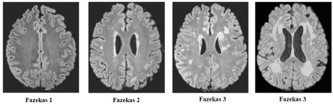

Participants were evaluated following a one-month period without the use of sedative medications (e.g., benzodiazepines), which are commonly prescribed to older individuals. All participants underwent 1,5 tesla MRI scans. The MRI protocol consisted of axial T1-weighted spin-echo images, axial, dual T2weighted Turbo spin-echo images and coronal fluid-attenuated inversion (FLAIR) images. For each image series, 20 slices covering the entire brain were obtained. White Matter hyperintensities were rated according to the Fazekas scale [11]. This is a scale of WMLs burden according to the lesions load (0: none or a single punctate lesion; 1: multiple punctate lesions=mild; 2: early confluence of lesions=moderate; 3: large confluent lesions=severe). WMLs were evaluated by lobe location, number and size. Automated quantification methods of to assess WMLs are rapidly evolving. This classification was proposed by Fazekas et al. in 1987 and at the time of writing (late 2016) it remains the most widely used system for describing white matter disease severity in publications. It is not generally used in clinical practice, with terms such as ‘mild’, ‘moderate’ and ‘severe’ being favored. Therefore, and should make it is easier to apply fine quantitative criteria for the sub-classification WMLs based on the anatomical and pathological criteria of WMLs, that comprises five areas, which supported a core region hypothesis in the central vestibular circuit: a) Subcortical area: prefrontal cortex frontal lobe, premotor cortex, frontal eye fields; b) deep periventricular; c) basal ganglia semioval center, corona radiata, caudate nucleus, globus pallidus, lentiform nucleus, thalamus, external capsule; d) parieto-insular vestibular cortex , retroinsular cortex, posterior insula, inferior parietal lobule, intraparietal sulcus, central sulcus; e) limbic system, cingulate anterior dorsal, hippocampus, amygdala, ipothalamic.

V-HIT results are outlined in Table 2. The estimates of peak location result from analysis of several neuroimaging of the WMLs, which can be subdivided in five major areas: a) subcortical area: frontal lobe, prefrontal cortex (34,6%); b) deep periventricular (34,6%); c) parieto-insular vestibular cortex (22,4%); d) basal ganglia: semioval center (22,4%), corona radiata (20,4%), caudate nucleus (6,1%), putamen (6,1%), globus pallidus (6,1%); e) thalamus (8,1%). By classification, we aim to make WMLs finding more relevant functionally. The Tab. III shows the classification and correlation between WMLs and central vestibular circuit. The Tab. IV, shows the Fazekas-scale provides an overall impression of the presence of WMH in the entire brain. On MRI, white matter hyperintensities (WMH) and lacunes both of which are frequently observed in the elderly are generally viewed as evidence of small vessel disease. It is best scored on transverse FLAIR or T2-weighted images (Figure 1). As expected, age was strongly associated with WMLs. Furthermore, sex, arterial hypertension, and diabetes were significantly associated with Fazekas scale (see Table 4. Demographic and clinical characteristics of the group as defined by amount of white matter hyperintensities.), which was not the case for hypercholesterolemia. The Table 5 illustrates the clinical characteristic of prespyvestibulopathy symptoms associated with Fazekas scale: postural imbalance (91,6%) and gait disturbance (83,3%) are associated with Fazekas 1 (focal lesion), while the chronic dizziness (79%) are associated Fazekas 2 (early confluent), finally the recurrent falls (10,4%) associated with Fazekas 3 (widespread changes in white matter). The data were also correlated of the v-HIT test with Fazekas scale: 41,6% (Fazekas 1), 47,9% (Fazekas 2) and 10,4% (Fazekas 3). Performance in v-HIT and results of the statistical analysis post hoc comparisons are illustrated in Tab. V. Fazekas groups 1 significantly in postural imbalance (91,6%) and gait disturbance (83,3%), while chronic dizziness (79%) is associated with Fazekas 2. Interestingly, only 5 patients had recurrent falls, all are related to the Fazekas 3 group.

Figure 1: Fazekas scale (White matter hyperintensities).

*The total number of small White Matter Lesion is greater than the number of patients (48 pts) because one patient can have more than one lesion. **Classification of white matter hyperintensities on the four stage Fazekas scale: The healthy brain (Fazekas 0), contrasted with punctiform (Fazekas 1), early confluent (Fazekas 2), and diffuse confluent (Fazekas 3).